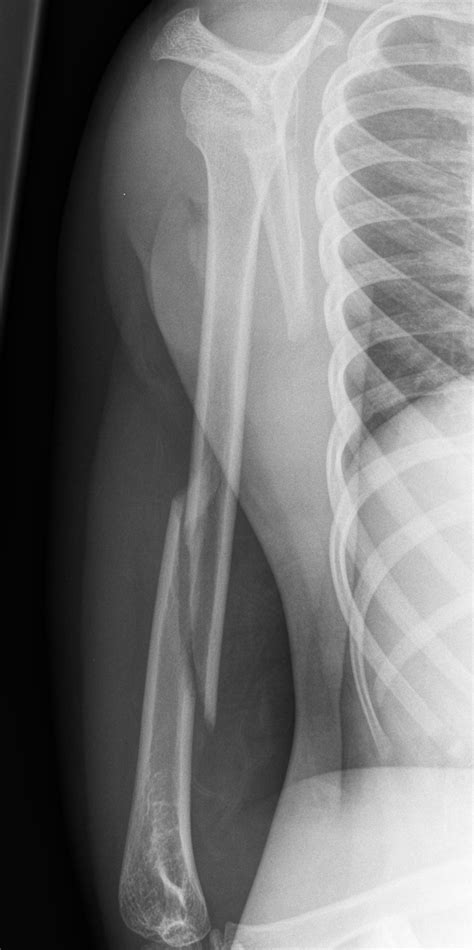

Diagnosing a Humerus Bone Break

Diagnosing a humerus bone break involves a combination of physical examination and imaging tests. The diagnostic process typically includes:

• Physical Examination: A healthcare provider will assess the arm for pain, swelling, and deformity.

• X-rays: Imaging tests such as X-rays are used to visualize the bone and determine the type and severity of the fracture.

• CT Scans or MRIs: In some cases, more detailed imaging like CT scans or MRIs may be required to assess the extent of the injury.